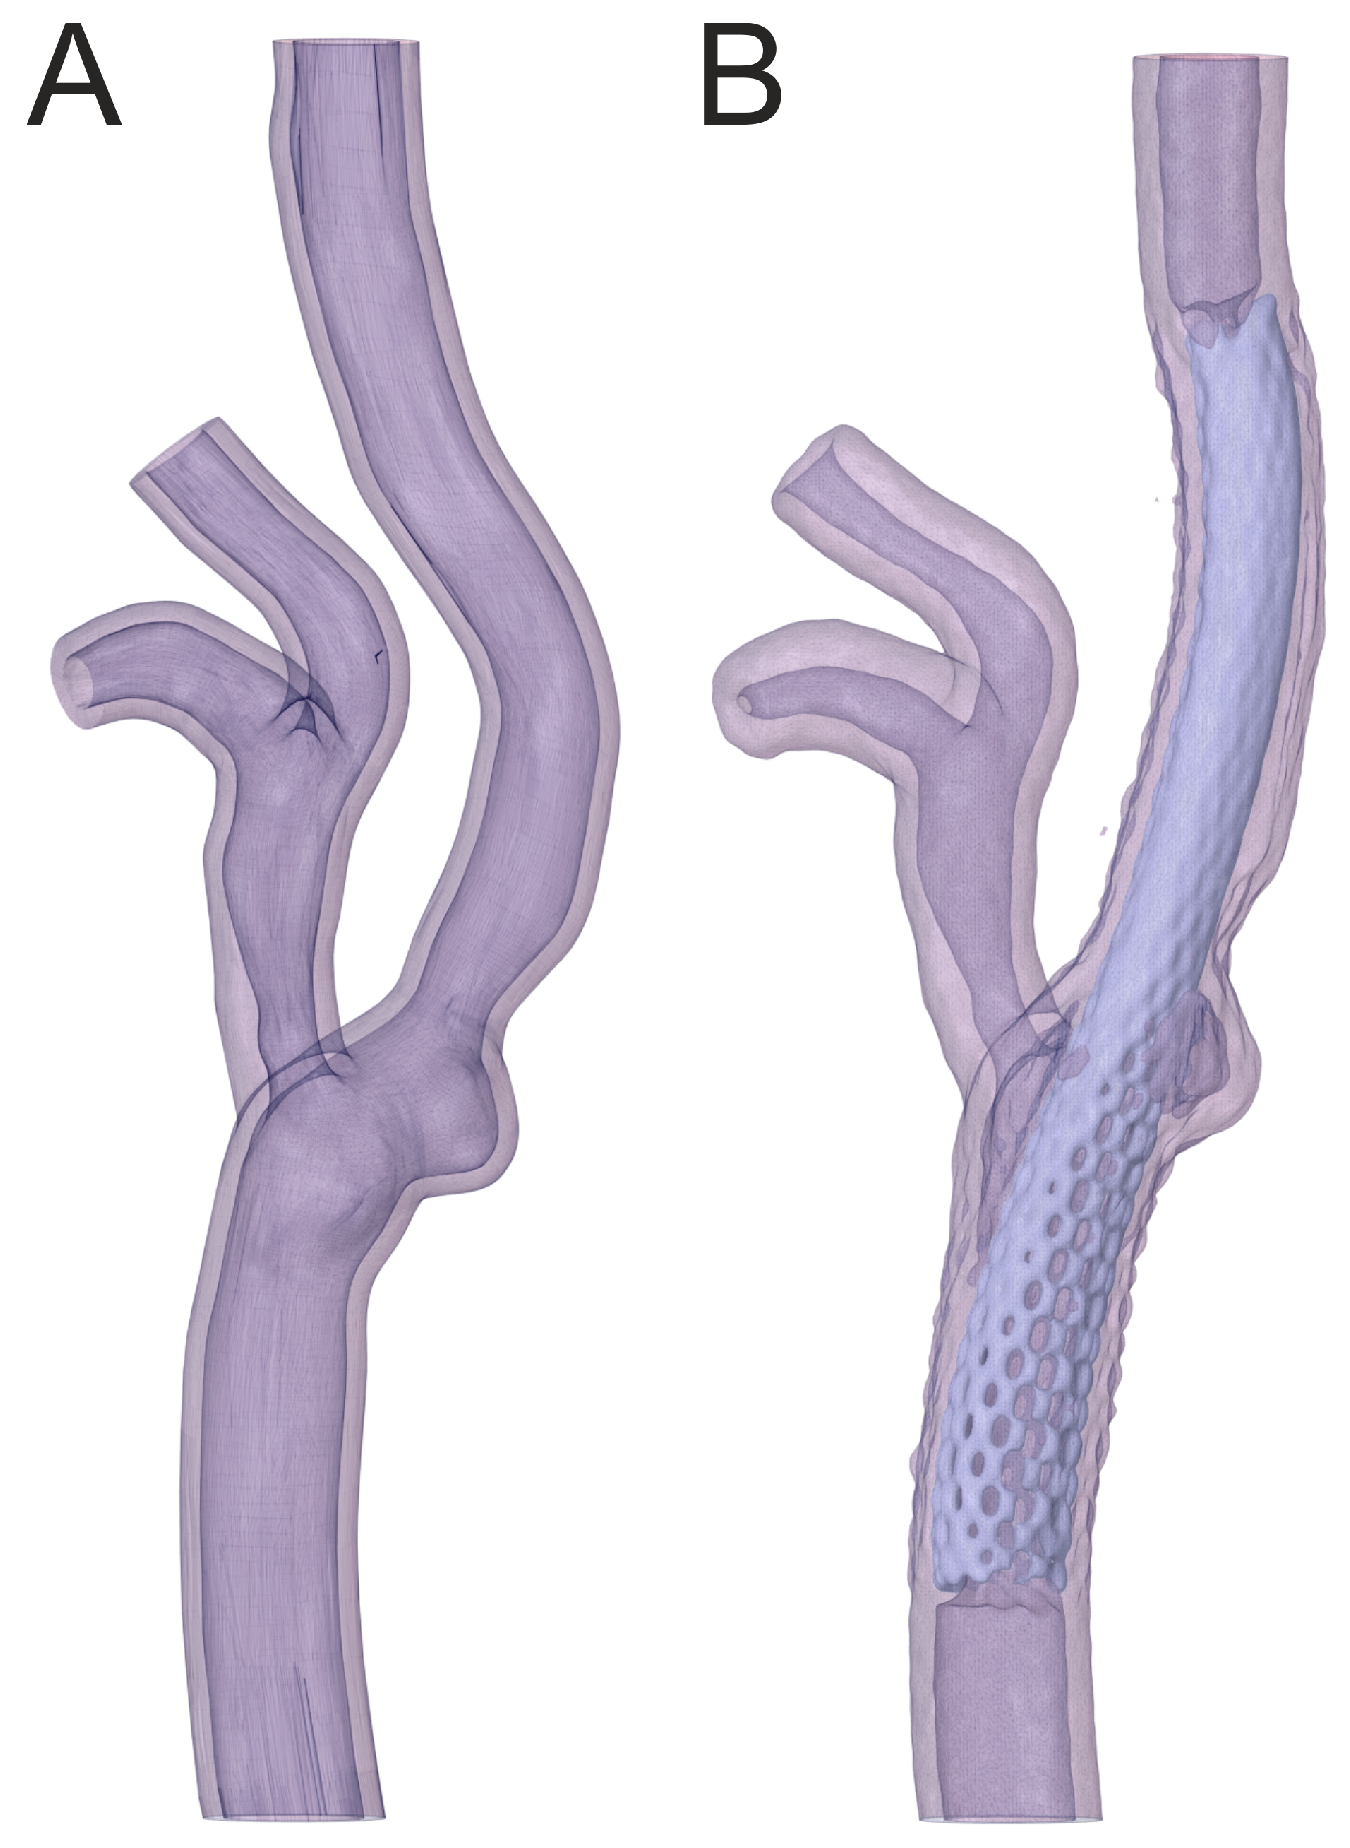

3.2. Percutaneous Carotid Artery Stenting on 3D-Printed Phantoms